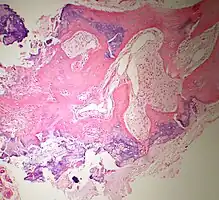

Histopathology

Bone Bizzare Parosteal Osteochondromatous Proliferation -

Bone Bizzare Parosteal Osteochondromatous Proliferation